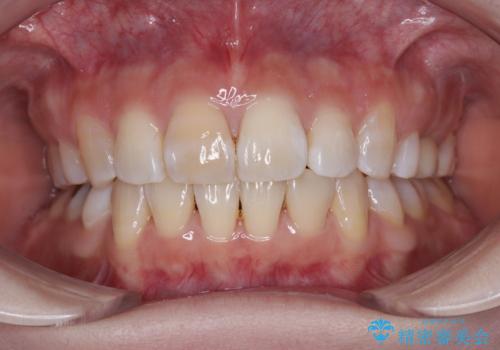

- (1)上顎前歯12本およ臼歯5歯

むし歯治療を実施し、矯正治療用の仮歯へ

初診から終了まで1年3ヶ月で、特に矯正歯科治療は被せ物に換える前提であったため8ヶ月間で終了することができました。

矯正歯科治療により、かみ合わせや歯並びを改善することができ、最も気にされていた歯の変色を自然な歯の色に仕上げることができ、大変満足していただけました。